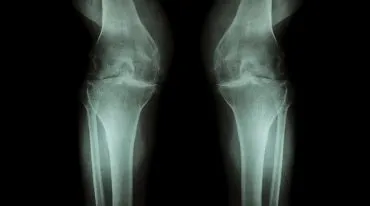

Wenn das Knie wieder knackt – Arthrose und ihre Ursachen